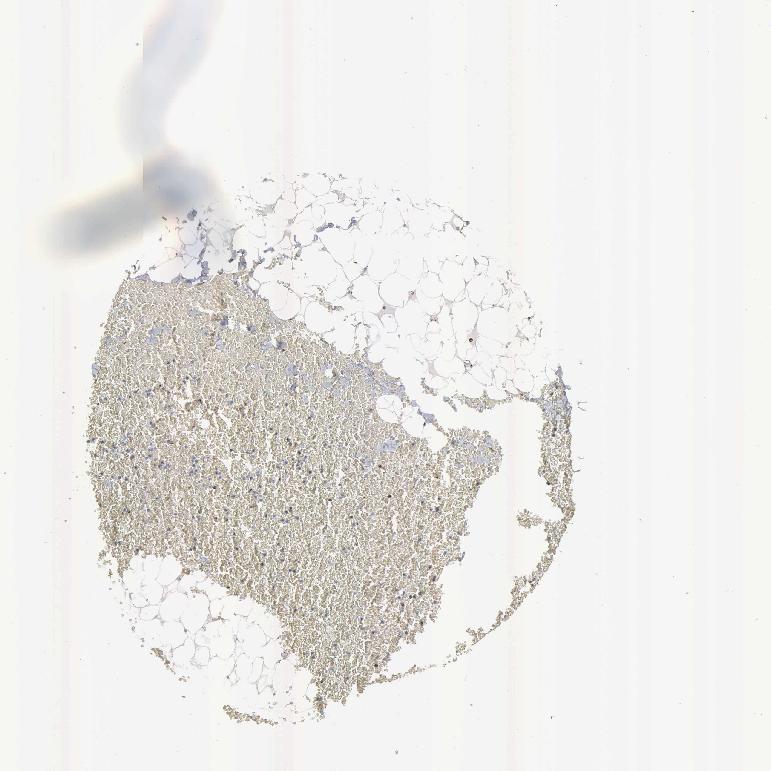

SOFT TISSUE 1 - Antibody stainingi

Antibody staining in the annotated cell types in the current human tissue is reported as not detected, low, medium, or high, based on conventional immunohistochemistry profiling in selected tissues. This score is based on the combination of the staining intensity and fraction of stained cells.

Each image is clickable and will lead to virtual microscopy that enables deeper exploration of all samples and also displays staining intensity scores, fraction scores and subcellular localization as well as patient and tissue information for each sample.

Antibody HPA000898Antibody CAB005219

Chondrocytes Medium-

Fibroblasts MediumHigh